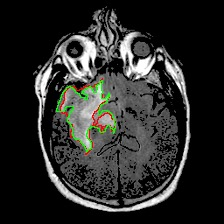

Neural processes have recently emerged as a class of powerful neural latent variable models that combine the strengths of neural networks and stochastic processes. As they can encode contextual data in the network's function space, they offer a new way to model task relatedness in multi-task learning. To study its potential, we develop multi-task neural processes, a new variant of neural processes for multi-task learning. In particular, we propose to explore transferable knowledge from related tasks in the function space to provide inductive bias for improving each individual task. To do so, we derive the function priors in a hierarchical Bayesian inference framework, which enables each task to incorporate the shared knowledge provided by related tasks into its context of the prediction function. Our multi-task neural processes methodologically expand the scope of vanilla neural processes and provide a new way of exploring task relatedness in function spaces for multi-task learning. The proposed multi-task neural processes are capable of learning multiple tasks with limited labeled data and in the presence of domain shift. We perform extensive experimental evaluations on several benchmarks for the multi-task regression and classification tasks. The results demonstrate the effectiveness of multi-task neural processes in transferring useful knowledge among tasks for multi-task learning and superior performance in multi-task classification and brain image segmentation.